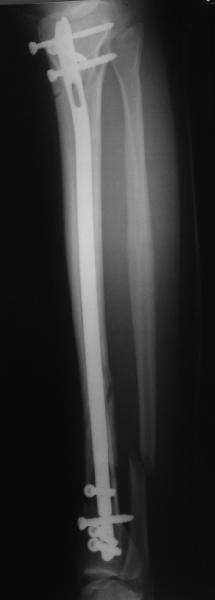

Сделали все-таки стержнем. На всякий случай просверлил дополнительное проксимальное отверстие, так что получилось три 45-градусных винта.

В дистракторе провеи спиц поболше в прокисмальном отделе, чтобы не разобщить фрагменты при сгибании колена. Комментарии и критика приветствуются.

We proceeded with nailing using a small wire distractor, with few wires at the proximal end to prevent displacement with forced knee flexion. Images attached. Comments and critics are welcome.

In this particlar case 4 frontal wires were inserted in anterior and posterior aspects at both sides of proximal fracture, and fixed to a single half ring with some bend to provide compression with wire tension. Image attached.

На одной опоре, расположенной чуть дистальнее обычного, были закреплены 4 спицы, проведенные во фронтальной плоскости, по 2 в передней и задней части смежных фрагментов. Закреплены так, чтобы при их натяжении создалась компрессия. Картинка в приложении.